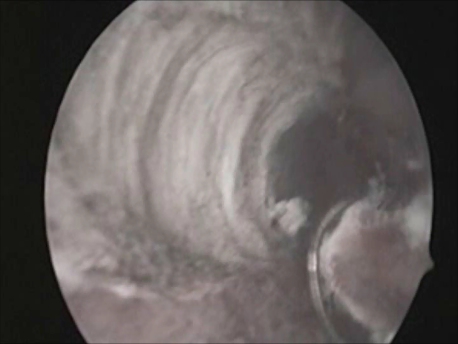

Endoscopy involves placing a small telescope into the human body through tiny incisions (3-5mm). The telescope can be placed into the abdomen via small tubes called ports (laparoscopy) or inside the uterus through the mouth of the uterus or cervix (hysteroscopy).